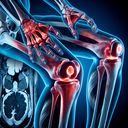

МРТ суглобів

Магнітно-резонансна томографія (МРТ) суглобів — це неінвазивне діагностичне обстеження, яке використовує магнітне поле та радіохвилі для отримання детальних зображень суглобів і навколишніх тканин. Ось основна інформація про МРТ суглобів: 1. **Мета:** - Виявлення пошкоджень кісток, хрящів, зв'язок, сухожиль і м'язів...